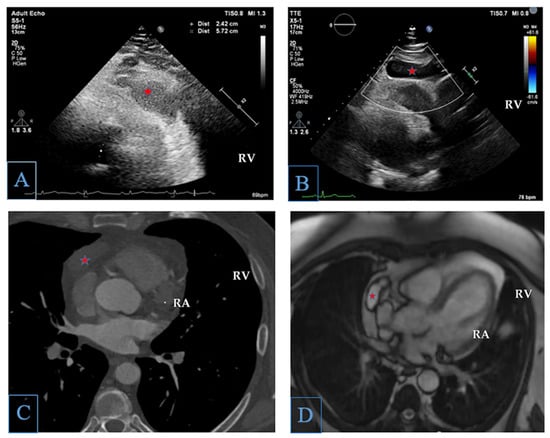

Right-Ventricle-Adjacent Mass: A Multimodality Imaging Approach to Diagnosis